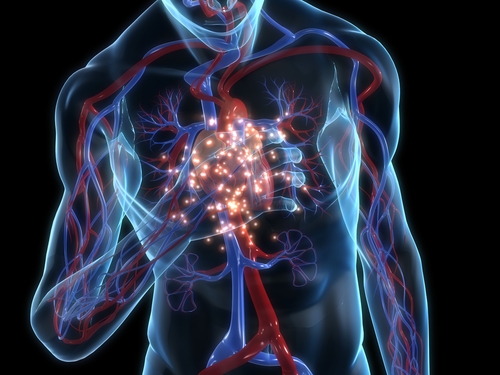

אנליזה בדקה את הבטיחות הקרדיווסקולרית, צרברו-וסקולרית ובכלי הדם הפריפריים של ארנומאב, לפי הוכחות ממחקרים שבדקו טיפול למניעת מיגרנה. נתונים לגבי תופעות לוואי וסקולריות ולחץ דם שולבו מ-4 מחקרים שונים, מחקרים מבוקרי אינבו שנערכו בסמיות כפולה ובדקו את הטיפול עם ארנומאב. כמו כן, נכללה ההארכה של מחקרים אלו עם תווית-פתוחה, במטופלים עם מיגרנה כרונית או אפיזודית. אנליזה של תתי-קבוצות נערכה לפי שימוש אקוטי בתרופות ספציפיות למיגרנה ולפי מספר גורמי הסיכון הוסקולריים שנצפו בשלב הבסיס ההתחלתי. תנאי סקירה סטנדרטים שימשו לזיהוי תופעות לוואי וסקולריות (קרדיווסקולריות, צרברו-וסקולריות או פריפריות). ועדה בלתי תלויה פסקה האם אירועי המטרה שנבדקו נגרמו ממקור וסקולרי.

במחקרים שנכללו באנליזה השתתפו 2,443 מטופלים, שקיבלו אינבו (1,043 מטופלים), ארנומאב במינון 70 מ"ג (893 מטופלים) או ארנומאב במינון 140 מ"ג (507 מטופלים), במתן תת-עורי פעם בחודש. ללא קשר לשימוש אקוטי בתרופות ספציפיות לטיפול במיגרנה או לגורמי סיכון וסקולריים שנצפו בשלב הבסיס ההתחלתי, שכיחות תופעות הלוואי הייתה דומה בין קבוצות הטיפול השונות. הן בקבוצה שנטלה אינבו והן בקבוצה שנטלה ארנומאב. תופעות לוואי של יתר לחץ דם דווחו ב-0.9% (בקבוצת האינבו), 0.8% (קבוצת ארנומאב 70 מ"ג) ו-0.2% (קבוצת ארנומאב 140 מ"ג) מהמטופלים. תופעות הלוואי הוסקולריות היו דומות בין אם הטיפולים ניתנו בשיטת הסמיות הכפולה לבין אם הטיפולים ניתנו בשיטת התווית הפתוחה. באופן כללי התוצאות היו מבלבלות, עם אטיולוגיות חלופיות סבירות. ב-18 מטופלים עם אירועים שנבדקו על ידי ועדה בלתי תלויה, 4 אירועים נפסקו כחיוביים ממקור קרדיווסקולרי: 2 מקרי תמותה ו-2 מקרים וסקולריים. כל ארבעת האירועים שנפסקו כקרדיווסקולריים התרחשו בזמן שניתן טיפול תווית-פתוחה עם ארנומאב.

מסקנת החוקרים הייתה כי לחסימה סלקטיבית של הקולטן הפפטידי הקנוני שקשור לגן הקלציטונין באמצעות ארנומאב למניעת מיגרנות, יש פרופיל בטיחות וסקולרי טוב. זאת בהשוואה לאינבו, במהלך 12 שבועות מעקב, ללא עליה בהופעת האירועים לאורך זמן. מחקרים נוספים נדרשים לבדיקת הבטיחות בטווח הארוך של ארנומאב, במטופלים עם מיגרנה.